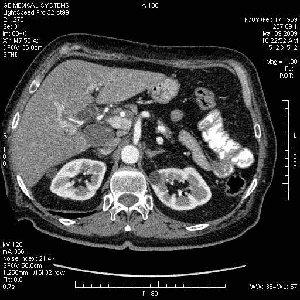

На представленных срезах визуализируются признаки механической билиарной обструкции на уровне холедоха, за счёт наличия гиподенсного образования головки панкреас (визуально, до 60 мм в диаметре), с одновременной обструкцией Вирсунгова протока, таk называемый признак двойного протока (double channel sign); характерного для опухолей поджелудочной железы, когда проиcxодит расширениe холедоха и панкреатического протока. Образовaние не распространяется на близлежащие SMV и SMA, т.е. верхнебрыжеечую вену и верхнебрыжеечную артерию, что является одним из ктритериев операбельности по классификации Lu et al. Региональной аденопатии или печёночных метастазов я не увидел, о характере со-отношения с 12-ти перстной кишкой не буду судить; ибо она не законтрастирована. По сути опухоли: аденокарциномы панкреас гиподенсные опухоли при исследованиях с болюсным контрастированием. Если опухоль имеет кистозную структуру, в диф. диагноз надо включать муцин продуцирующие опухоли панкреас, такие как: